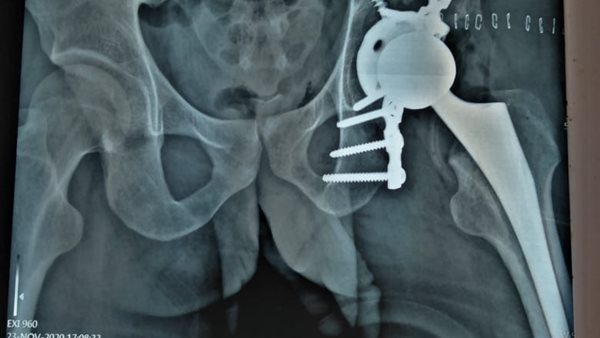

استبدال مفصل كامل بآخر صناعى لشاب بمستشفى المنصورة الدولى.. صور

17/02/2021 04:39 ص